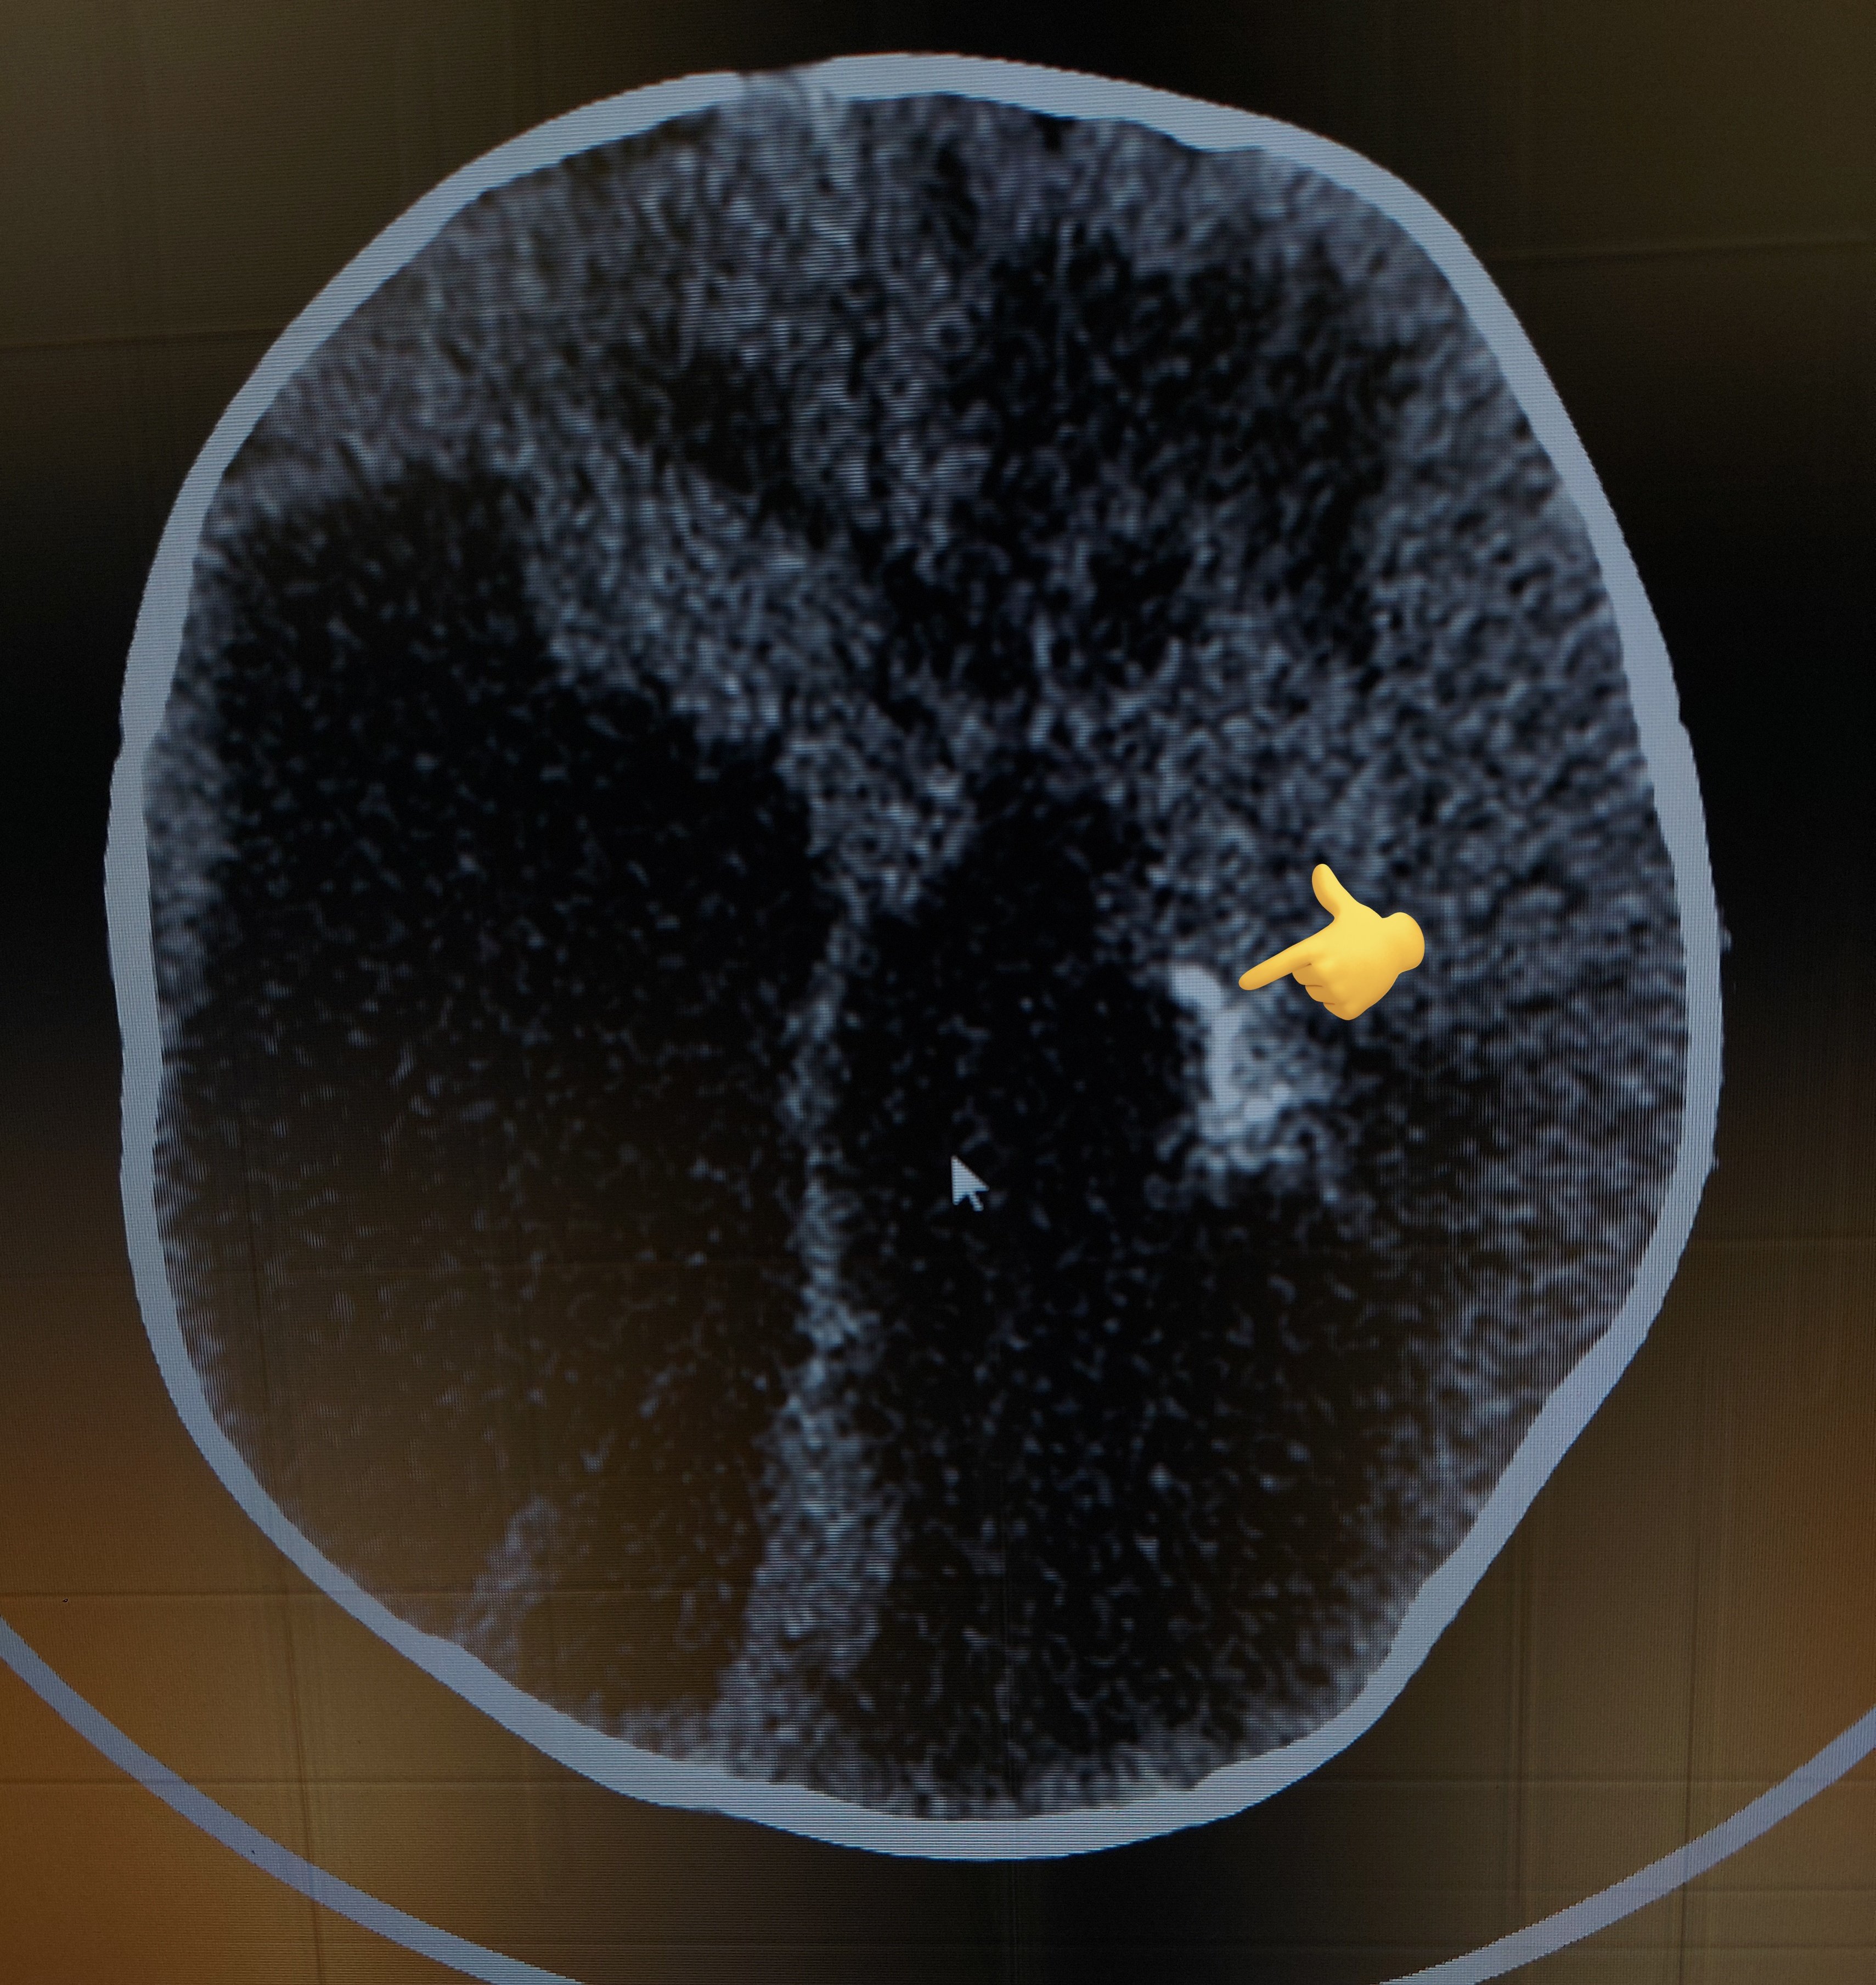

From twitter.com

Rajesh S on Twitter "9 month old kid with enlarging head size🙇♂️ ☣ Torch Infection Hydrocephalus congenital torch infections comprise a group of diseases that affect the fetus and the newborn. Infections acquired in utero or during the birth process are a significant cause of fetal and. the torch infections include causative organisms toxoplasma gondii, rubella virus,. in case of fetal infection, early diagnosis and prolonged postnatal treatment improve children’s prognosis and consist. Torch Infection Hydrocephalus.

Rajesh S on Twitter "9 month old kid with enlarging head size🙇♂️ ☣ Torch Infection Hydrocephalus torch is an acronym that denotes a chronic nonbacterial perinatal infection. the torch infections include causative organisms toxoplasma gondii, rubella virus,. in case of fetal infection, early diagnosis and prolonged postnatal treatment improve children’s prognosis and consist of. congenital torch infections comprise a group of diseases that affect the fetus and the newborn. It stands for. Torch Infection Hydrocephalus.